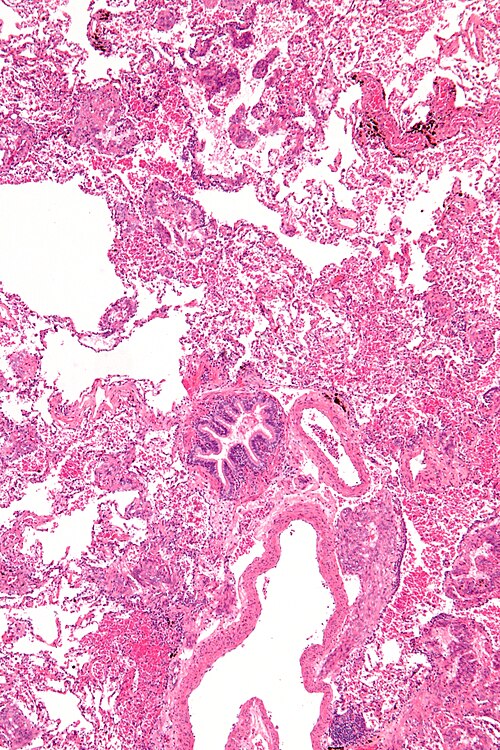

Primary image

Low magnification. H&E stain.